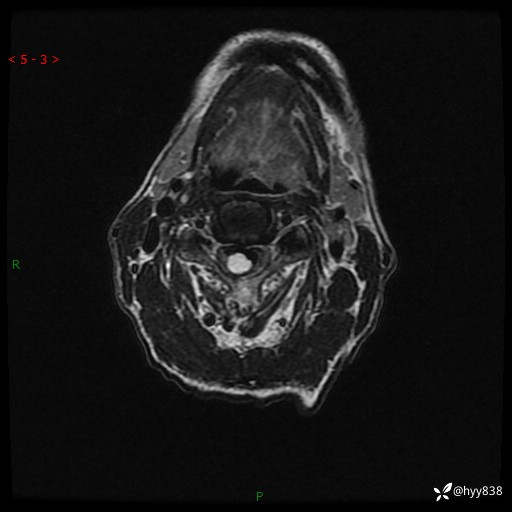

颈椎MRI平扫(sag T1WI+T2WI-fs+axi T2WI)

辅助检查:MRI

临床诊断:椎管占位